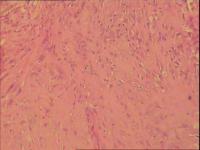

骨巨细胞瘤1级

膝关节置换术后7年,疼痛6月。 术中见关节假体周围大量增生肉样、葡萄状组织。是否有骨质浸润手术医生说不清楚,X片未见骨质浸润。

膝关节腔内肿物

灰白组织一堆直径7cm,部份组织呈葡萄样。

那些颗粒状物是假体脱下来的碎屑,巨细胞首先考虑是反应性的。

会诊意见:见大量组织细胞,多核j巨细胞反应,未见明确肿瘤性病变。